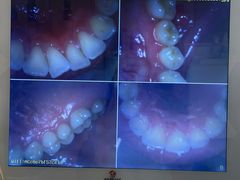

• 好大夫口腔(广州店)

• -好大夫口腔(广州店)

匿名用户 | 24-01-05